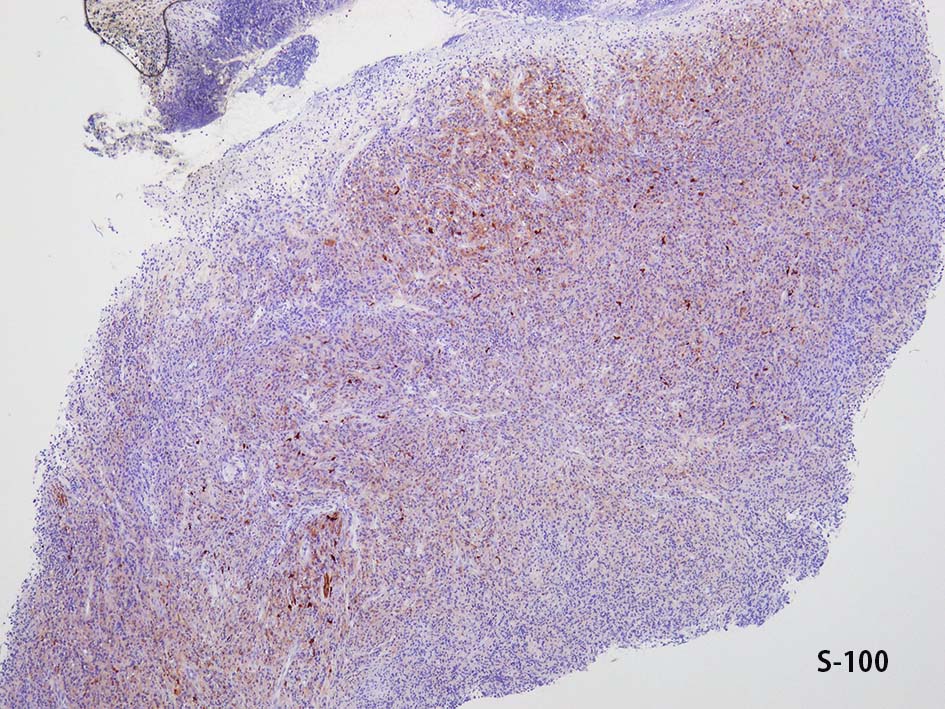

免疫染色

CD20, PAX5, CD3, CD5 リンパ球マーカは陰性. Dendritic cell marker (CD1a, CD123, Langerin, etc)は陰性. S-100, CD168が陽性. 組織球増殖病変と考えられた. foamy macrophageやgiant cellsはほとんど認められない. 高異型度, 多型細胞の出現はないが, MIB-1 LIが高く, mitosisも増加している, 悪性の心配あり, 治療方針の決定のため consultationを行った.